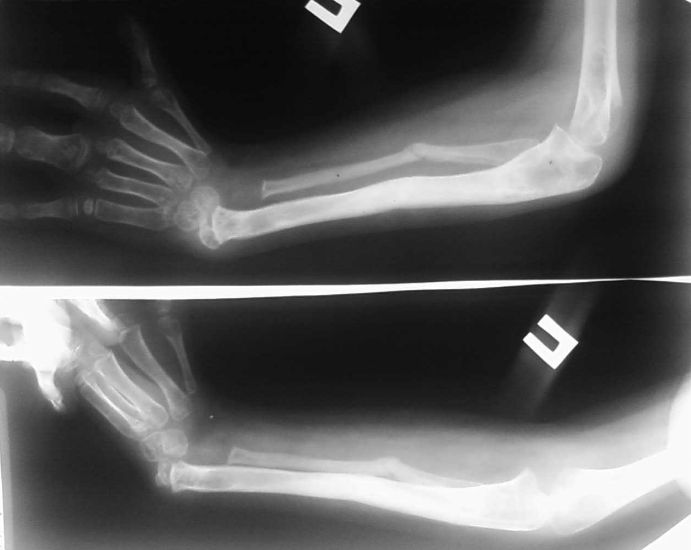

Вроджена косорукість – стійка деформація, в результаті якої кисть відхиляється в ліктьову або променеву сторону від поздовжньої осі передпліччя. Виникає у внутрішньоутробному періоді. Є наслідком недорозвинення однієї з кісток передпліччя або асоційованих з цими кістками сухожиль. Виявляється викривленням верхньої кінцівки – кисть розташована під кутом до передпліччя. Може поєднуватися з недорозвиненням п’ясткових кісток, фаланг пальців, відсутністю одного або декількох пальців, зрощенням пальців, контрактурами, підвивихами або вивихами в ліктьовому і лучезапястном суглобах. Діагноз виставляється на підставі рентгенологічної картини і даних об’єктивного дослідження. Лікування хірургічне, проводиться в ранньому віці (зазвичай до 1 року). Після операції призначається ЛФК, масаж і фізіотерапія.

Виділяють два типи вродженої косорукості: променеву та ліктьову. Променева косорукістю формується при недорозвиненні або відсутності променевої кістки і асоційованих з нею сухожиль, ліктьова – при недорозвиненні або відсутності ліктьової кістки і відповідних сухожиль. Кожен тип вродженої косорукості підрозділяється на кілька підтипів з урахуванням ступеня недорозвинення кістки.

При променевої косорукості кисть знаходиться в положенні пронації, між пензлем і передпліччям утворюється кут, відкритий в сторону променевої поверхні (сторону великого пальця). За тильній поверхні виявляється проксимальное зміщення кисті по відношенню до голівки ліктьової кістки. Кисть обертається навколо головки, як прапорець флюгера.

Передпліччя зазвичай укорочено, головка ліктьової кістки виступає. Через деформації ліктьової кістки виникає дугоподібне викривлення передпліччя з опуклістю, оберненою в ліктьову сторону (бік V пальця). М’язи передпліччя недорозвинені. Пронатори і супінатори передпліччя, довгі м’язи I пальця і плечелучевая м’яз нерідко відсутні. Можливо також відсутність довгої головки біцепса плеча. При аплазії променевої кістки також спостерігається відсутність променевої артерії.

При ліктьовий косорукості кисть знаходиться в положенні супінації, між пензлем і передпліччям утворюється кут, відкритий в ліктьову сторону (бік V пальця). V і IV пальці часто відсутні або недорозвинені. Передпліччя укорочено. Через деформації променевої кістки утворюється дугоподібне викривлення, звернене опуклістю в променеву сторону (бік I пальця). Рухи в ліктьовому суглобі обмежені через вивиху головки променевої кістки. М’язи передпліччя з ліктьової сторони недорозвинені або відсутні. Функція кисті порушена менше, ніж при променевої косорукості.

Постановка діагнозу вроджена косорукістю технічно нескладне труднощів через візуально видимих деформацій і явних порушень функції кінцівки. Для точної оцінки ступеня недорозвинення кісткових структур і уточнення подальшого плану лікування виконують рентгенографію кісток передпліччя і рентгенографію кісток кисті. Для оцінки стану м’яких тканин призначають МРТ передпліччя і електроміографію.